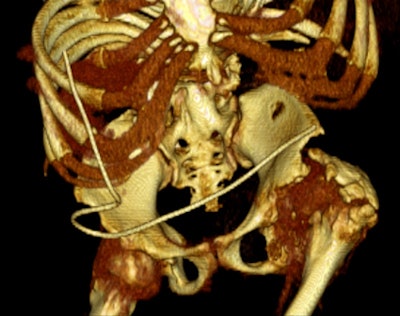

Left: A 33-year-old male with spina bifida. Reconstructed coronal maximum intensity projection CT image shows bilateral staghorn calculi and horse-shoe kidney. Right: A 37-year-old male with spina bifida. 3D reconstruction demonstrates the logistical difficulties with imaging, treatment, and management due to gross bony deformities. Images courtesy of Dr. Sanjay Agarwal.Currently, there is ongoing research for management of neurogenic bladder dysfunction. In the short term, simple things such as safer tube drainage using biofilm blocking and dispersive agents and closed tube drainage systems may help with reducing infection rates. More complex research is being conducted from multiple angles -- for example, application of gene therapy (use of herpes simplex virus-derived vectors, etc.), development of newer medication (afferent pathway drugs) and tissue regeneration (tissue-engineered autologous augmentation cystoplasty). All will have roles to play in future management of these patients, making this a very exciting time, Agarwal pointed out.